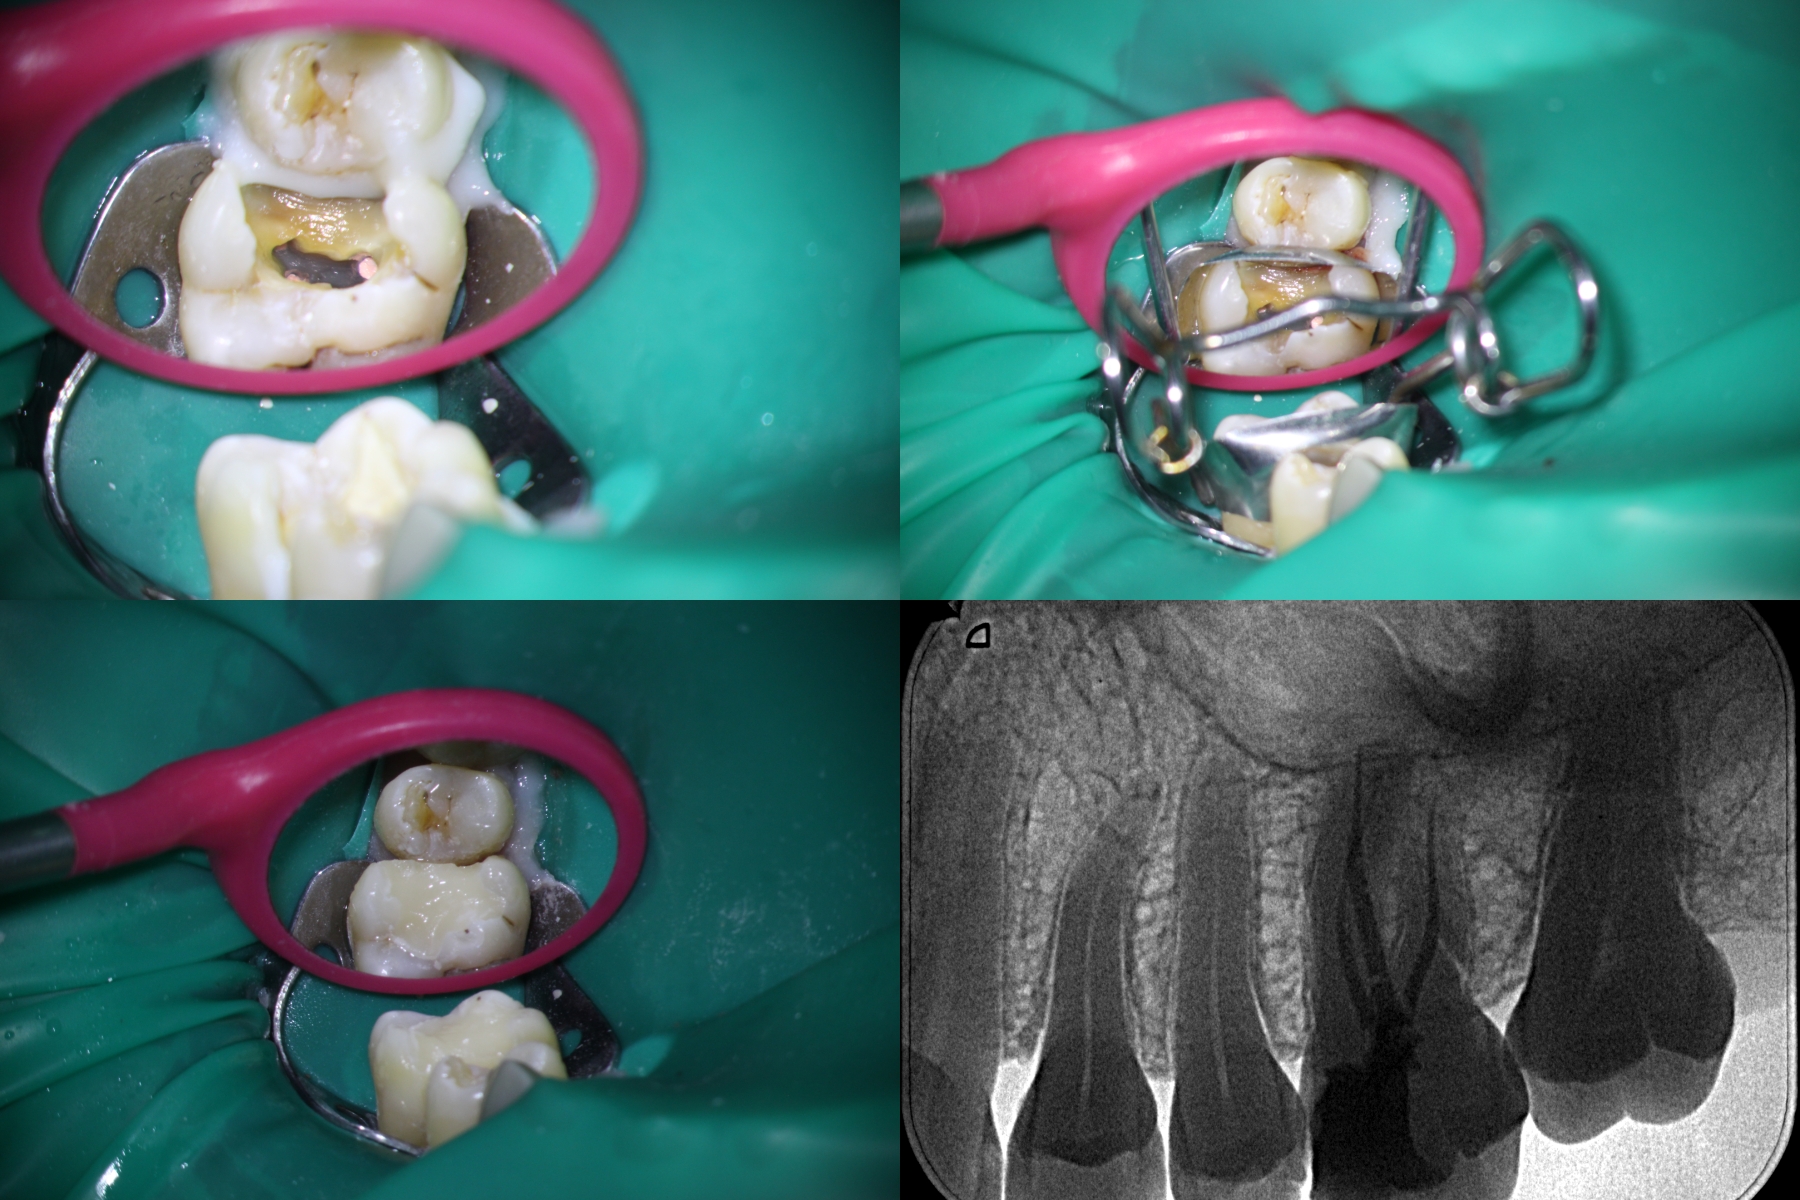

Revathi Miglanis exploration of RCT on maxillary molars with Carabelli cusp is commendable providing a nuanced perspective.

surprised with the pictures of Carabelli’s upper molars. A difficult case for the dentist. flappy bird game

Based on these images, it can be concluded that the jaw tooth has damaged pulp and needs urgent treatment by filling. Suika game